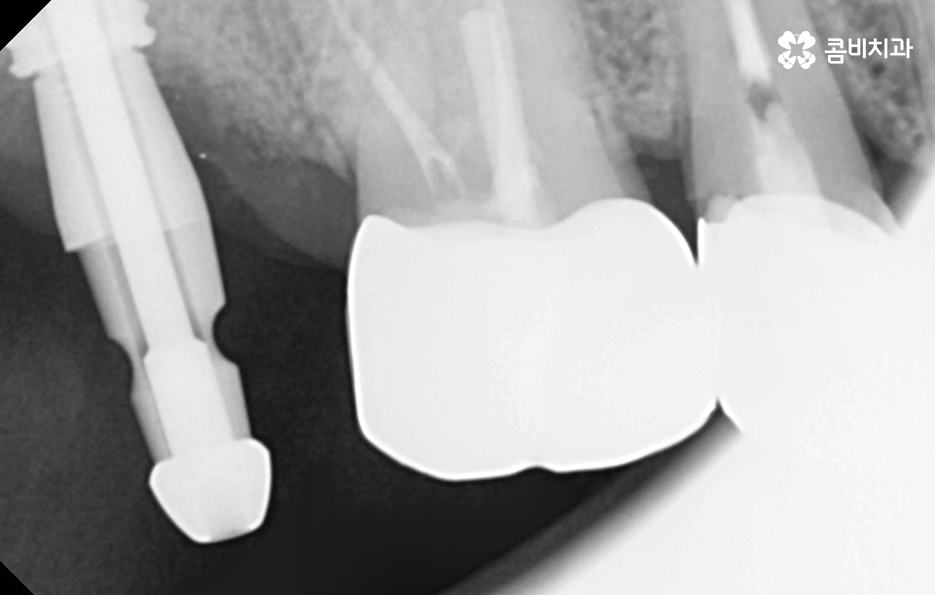

어금니 충치 발치 후에는 바로 임플란트를 해야 하나요

위 사진에서 보여지는 것처럼 어금니는 치아 안쪽에 위치하고 있기 때문에 치아 상실 후에 심미적인 부분에 있어서는 당장 불편함을 못느낄 수 있지만 치아는 저마다 역할과 기능이 있고 저작력에 있어서 밸런스도 무척이나 중요하기 때문에 치아를 잃게 되었다면 별다른 이유가 없다면 즉시 임플란트 치료 계획을 세우시길 권하고 있어요

당장은 반대쪽 어금니로 식사를 해도 괜찮다고 느끼시는 분들도 있지만 장기적으로는 치아 저작력의 밸런스를 잃게 될 수 있고 그로 인해 소화불량이나 턱 관절 장애로도 이어질 수 있는데요. 임플란트를 즉시 권하는 더 중요한 이유로는 치아 발치 후에는 해당 잇몸 뼈가 서서히 흡수되기 때문에 주변 치열이 망가지거나 반대쪽 치아가 내려올 수 있으며 추후에는 임플란트를 하더라도 잇몸 뼈의 부족으로 인해 뼈이식을 추가적으로 해야 할 수 있다는 점에서도 임플란트 치료를 미루지 마시길 권하고 있어요